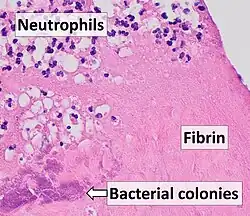

Damaged valves and endocardium contribute to the development of infective endocarditis.[38] Specifically, the damaged part of a heart valve forms a local blood clot, a condition known as non-bacterial thrombotic endocarditis (NBTE). The platelet and fibrin deposits that form as part of the blood clotting process allow bacteria to take hold and form vegetations. As previously mentioned, the body has no direct methods of combating valvular vegetations because the valves do not have a dedicated blood supply. This combination of damaged valves, bacterial growth, and lack of a strong immune response results in infective endocarditis.

- Histology or culture of cardiac vegetation, embolized vegetation, or intracardiac abscess from the heart finds microorganisms